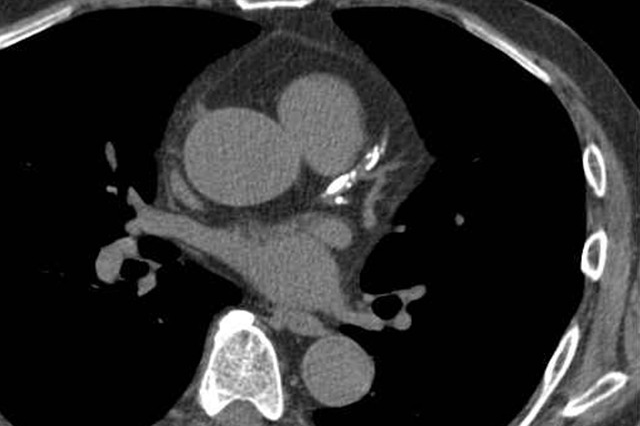

복부 컴퓨터단층촬영(Computed Tomography, CT)은 고해상도의 X‑ray 단면 영상을 빠르게 획득해 복부 내부 장기의 구조·질환을 정밀하게 분석하는 영상의학 검진법입니다. 초음파나 단순 X‑ray보다 해상도가 높아 미세 병변도 쉽게 확인할 수 있어 응급실·외래·건강검진센터 등에서 폭넓게 활용됩니다.

특히 간·담도·췌장·신장 같은 실질장기뿐 아니라 장관·혈관·복막까지 한 번에 관찰할 수 있다는 점이 최대 장점입니다.

- 간동맥기, 문맥기, 지연기 등 다상 촬영으로 병변 감별력을 향상